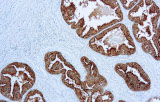

Los anticuerpos validados CE/IVD diseñados para flujos de trabajo diagnósticos de IHQ se utilizan ampliamente para apoyar protocolos de tinción estandarizados y reproducibles en laboratorios clínicos. Estos reactivos son particularmente relevantes para laboratorios de patología que operan en entornos diagnósticos regulados donde se requiere fiabilidad analítica y cumplimiento normativo. Desde una perspectiva científica, la IHQ funciona como complemento a la histomorfología al resaltar proteínas específicas de linaje, marcadores de diferenciación celular y antígenos tumorales asociados que definen las neoplasias genitourinarias.

Estandarización para laboratorios clínicos

Los anticuerpos CE/IVD apoyan flujos de trabajo de tinción e interpretación estandarizados, alineándose con prácticas diagnósticas guiadas por guías descritas en revisiones de patología genitourinaria.